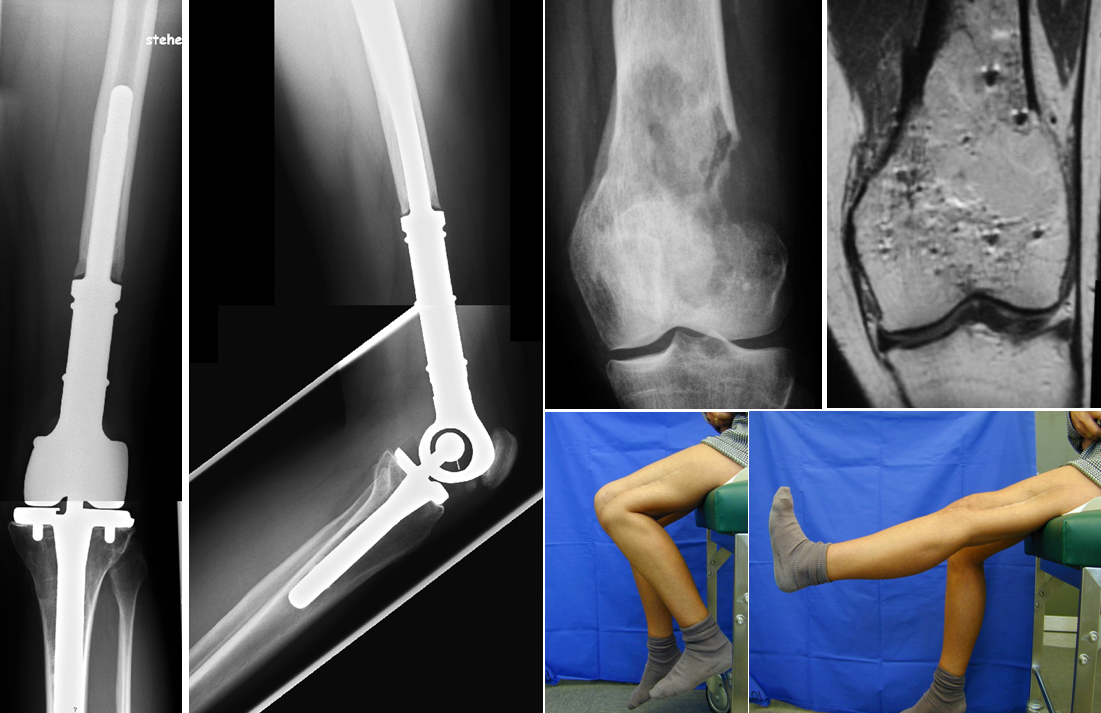

24-jährige Patientin mit periostealen Osteosarkom (G1) des distalen Femurs. Tumorprothese, 10-jähriger Verlauf.